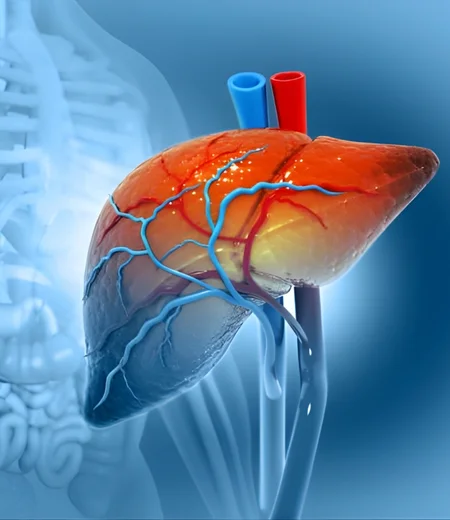

Liver and bile duct cancers are serious conditions that affect essential organs involved in digestion, detoxification, and metabolism. Due to their complex location and close proximity to major blood vessels, these cancers often require highly specialized surgical expertise. Surgical removal of the tumor remains the most effective option for improving long-term survival.

Liver & Bile Duct Cancer Surgery

Liver Resection (Hepatectomy)

Removal of the cancerous portion of the liver while preserving healthy tissue.